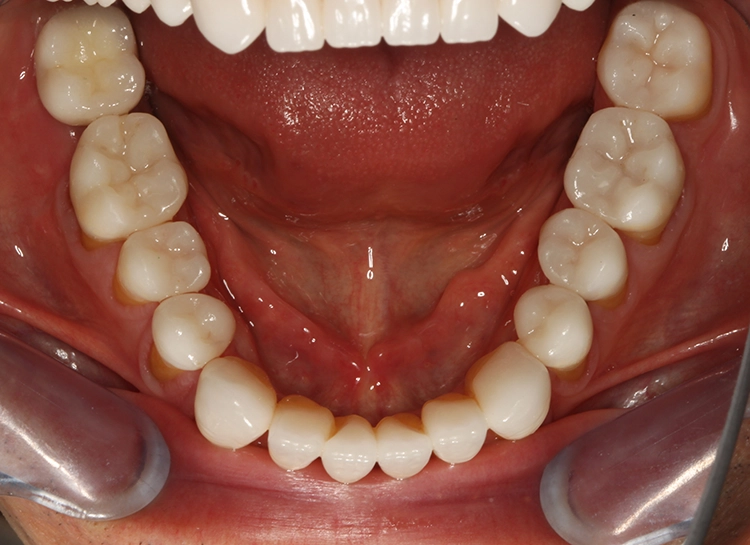

Egger/Wermuth/GrevenRote Ästhetik: Im Ober- und Unterkiefer zeigten sich generalisiert ausgedehnte Rezessionen mit bis zu 8 mm Attachmentverlust vor allem im Bereich der Eckzähne (Miller-Klasse III; Rezessionstyp [RT] 2 [69]. Das Band an keratinisierter Schleimhaut ist durchgehend vorhanden. Die Breite variiert im Eckzahnbereich von 1 mm bis zu 2 mm im Bereich der Unterkieferfrontzähne, der Prämolaren und Molaren (Abb. 1). Die fazialen Rezessionen sind mit approximalem röntgenologischem Attachmentverlust im koronalen Wurzeldrittel (Abb. 2) und Papillenverlust im Bereich zwischen den Kontaktpunkten und der approximalen Schmelz-Zement-Grenze assoziiert (Abb. 1). Der Patient verfügt über eine schmal geformte Oberlippe. Die Lachlinie verläuft mittelhoch (Abb. 3).

Dentalstatus: Es zeigen sich generelle Abrasionen, Attritionen und Erosionen im Ober- und Unterkiefer. Die ursprüngliche anatomische Kauflächenstruktur in den Seitenzahnbereichen ist durch die massiven erosions- und attritionsbedingten Zahnhartsubstanzverluste nicht mehr vorhanden (Tab. 2). Aufgrund der massiven Zahnschmelzverluste erscheint die Zahnfarbe insgesamt gelblicher. Der Patient wünscht sich im Rahmen der Rehabilitation in dieser Frage eine merkliche Verbesserung.

Parodontale Gesundheit bei Attachmentverlust, Bruxismus, Erosion. Abbildung 1 sowie 6 bis 9 zeigen den Anfangsbefund als intraoralen Fotostatus.*